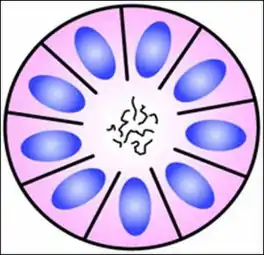

Homer Wright pseudorosette

A Homer Wright pseudorosette is a type of pseudorosette in which differentiated tumor cells surround the neuropil.[15] Examples of tumors containing these are neuroblastoma, medulloblastoma, pinealoblastoma, and primitive neuroectodermal tumors of bone. Homer Wright rosettes are considered "pseudo" in the sense that they are not true rosettes. True rosettes are Flexner–Wintersteiner rosette, which contain an empty lumen. Homer Wright rosettes contain abundant fibrillary material. They are named for James Homer Wright.

Structure of a Homer Wright pseudorosette

Structure of a Homer Wright pseudorosette